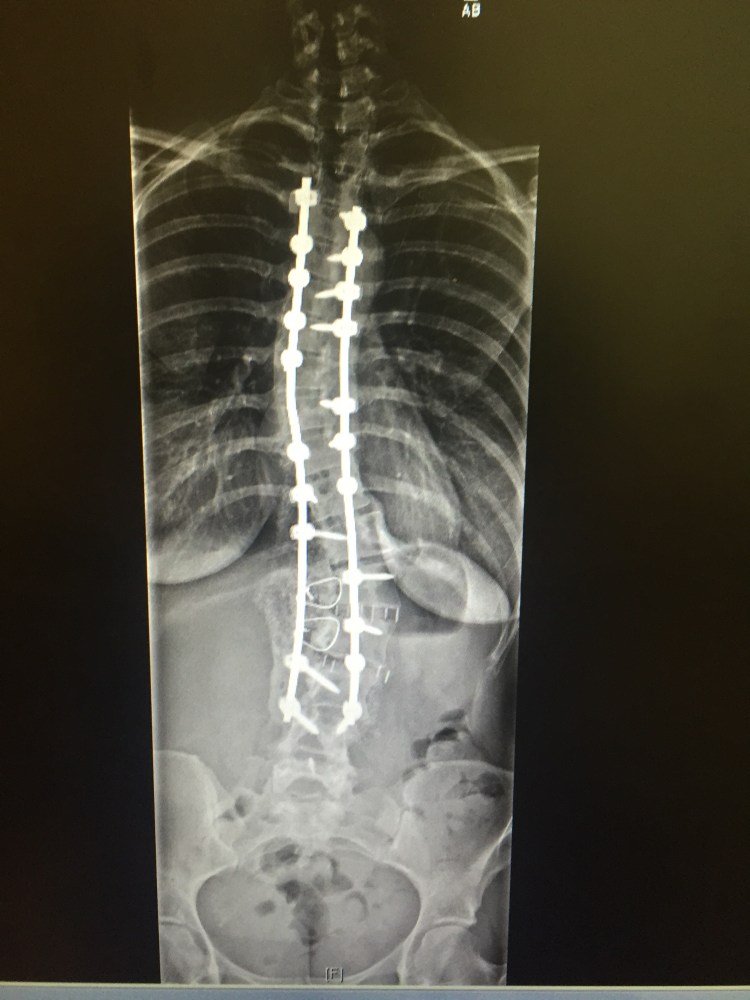

On Wednesday, I saw my spine doctor for my first post-op. While walking in, a lady that works in the lobby saw me using a walker and came to find me in line for check in. She asked if I wanted two tennis balls to put on the bottom of my walker. It’s official, I am getting a pair of white Velcro shoes and heading down to the bingo ranch. Apparently it makes it easier and much smoother to handle. I was called back for X-rays and Will was very upset he couldn’t accompany me into the room. First I had to change into a gown and robe which made for a super difficult and depressing experience. Sometimes, even though I am limited on what I can do, I often will have moments where I forget. After talking everything off and getting the gown and robe on, I realized that I can’t pick my shoes and pants up! I tried to get my foot up underneath them and kick them up but sadly I just couldn’t do it. I started to tear up but quickly calmed myself down. I finally peered out of the little dressing room and asked a little old lady if she could possibly pick them up for me and help move my back brace to a chair while I limp over in the walker. After X-rays, I headed over to the room where I met Neil and the boys. Besides the moment where Will was yelling that I threw up in the diaper bag a few days prior, they were so amazingly good! I can’t believe it we are 2 for 2 in a row! We talked about my left leg, lowering my pain medicine , outpatient PT after my in home PT and of course the x-rays. The x-rays actually showed my spine to have gotten a tiny bit straighter since the post surgery x-rays. That’s some really great news! We did talk about my right shoulder being higher than the other and my ribs not being even. Since my body had adapted to being straight despite the awful crookedness of my spine, once my spine was corrected it caused my deformed rib cage to be uneven. She did notice this during surgery and put a hook in on my right side to try and pull that shoulder down. I knew it was never going to be perfect and my body has a long way to go until we really see the finished product. I just need to power through this next year even though I have moments where I feel like giving up. Giving up is not an option.

Hi Sue, I did not have a virus. That is what the ER Doctor said because he had no idea what he was talking about. I honestly hate going to the ER. I feel like it’s such a waste of money. We had to fork over $350 bucks even though I have now reached our limit. It was my bowel that was spasming for 13 plus hours because of all the laxatives and various things they had me on and my colon and bowel couldn’t take it. As for the hook, at the top of my rods she put a hook in to my right side on top and tightened it to the rod to try and pull that right shoulder down and anchor it in. Not sure if that makes much sense.